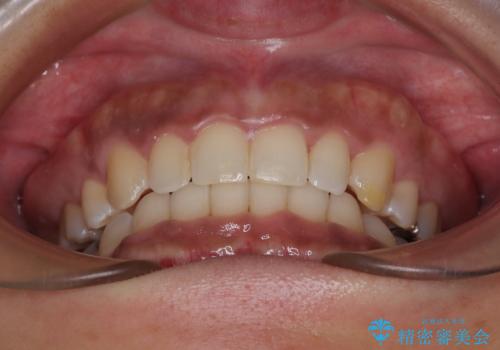

抜歯矯正で口が閉じやすく|ディープバイトと叢生を改善した症例

- 下顎前歯部には叢生が認められ、口を自然に閉じにくい状態でした。また、噛み合わせが深い「ディープバイト」の状態で、見た目だけでなく将来的な奥歯への負担も懸念されました。

口元の突出感を改善するため、上下左右の小臼歯4本を抜歯する矯正治療を計画しました。